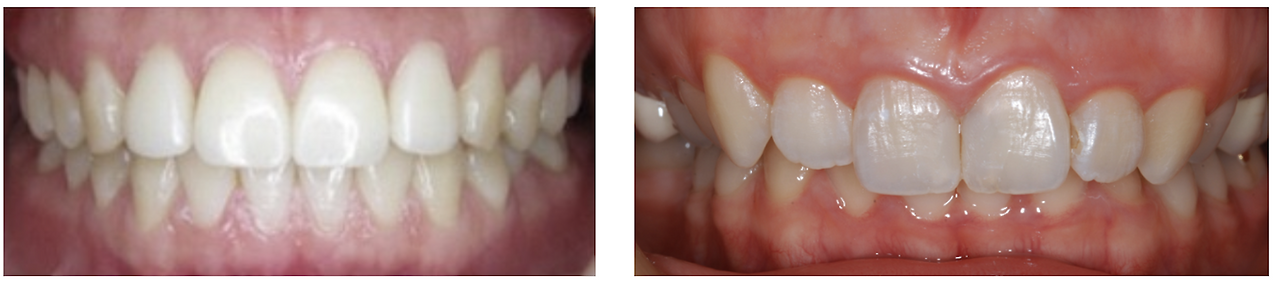

턱이 뒤로 밀리는 양상으로 윗치아가 아래치아를 많이 덮는 부정교합을 과개교합(deep bite)이라고 합니다. 과개 교합의 경우 두통, 중이염, 턱관절 잡음의 발생과 매우 관련이 많으며 밀린 아래턱에 의해 airway가 좁아지고 압박되는 현상이 만들어집니다. 이를 보상하기 위해 만드는 목을 앞으로 쭉 빼는 전방 두부 자세(head foward posture)를 취하게 됩니다. 거북목, 일자목이라고 칭하는 자세말이죠.

왼 쪽 : 정 상 교 합 / 오 른 쪽: 과 개 교 합